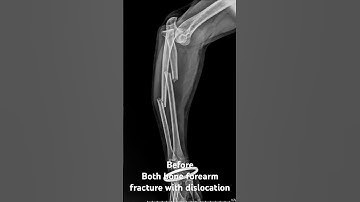

Maluniting fracture both the bones forearm | treated elsewhere, corrected | short GA | Adamya Hosp V